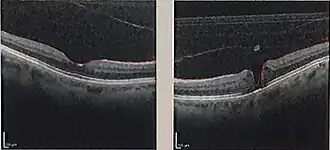

![]() Tomografía de coherencia óptica de un agujero macular (derecha), comparado con una mácula normal | ||

La exploración oftalmológica hace posible establecer el diagnóstico. Existe una prueba denominada tomografía de coherencia óptica (OTC) que permite obtener imágenes de gran precisión, mediante las cuales se puede averiguar el grosor de la retina, la presencia de agujero macular y su grado de evolución.